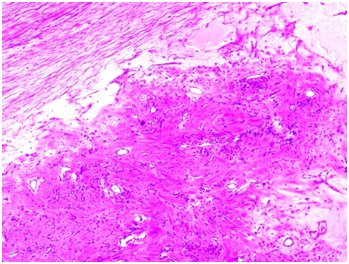

Based on the above described findings, the lack of guidelines and misleading clinical symptoms, our tumor board decided to offer the patient a laparotomy with left salpingo-oophorectomy. We performed an infraumbilical incision of the abdomen. The right ovary and uterus were macroscopically normal. Gross examination showed a marked left ovarian enlargement with smooth white external surface. The uncertainty of malignant potential due to the size of the lesion was the reason to perform a salpingo–oophorectomy. En bloc resection of the tumor was performed. One litre of clear fluid emerged after the incision of the surface. Microscopic examination revealed marked oedema of ovarian stroma with its architecture preserved. Normal germinal follicles were present without signs of necrosis but abundant cystic lesions were seen on the upper surface of the ovary (Figure 2) (Figure 3).

Figure 2 Fibroblastic stroma with lymphatic channels. Stromal oedema on the left.